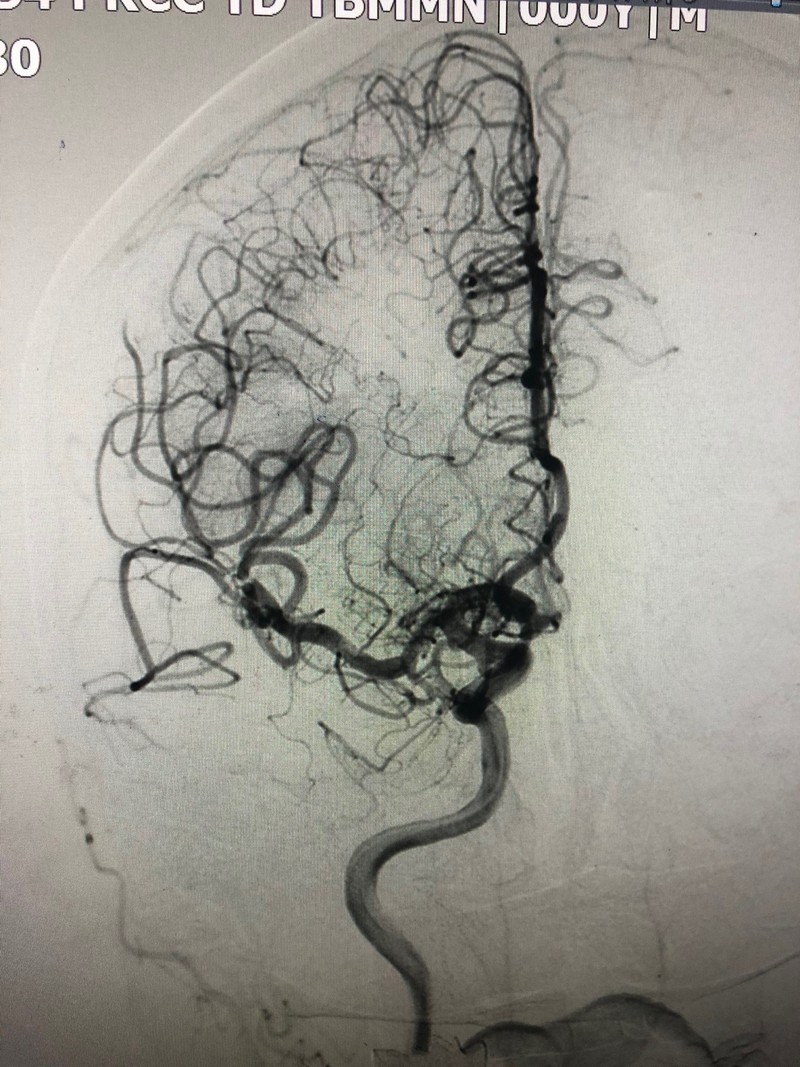

Sau can thiệp, bệnh nhân đã được cải thiện tình trạng liệt khá tốt và được tiếp tục điều trị nội khoa cũng như phục hồi chức năng sớm để hạn chế di chứng.

Tái thông động mạch não giữa sau can thiệp lấy huyết khối. Ảnh: BVCC